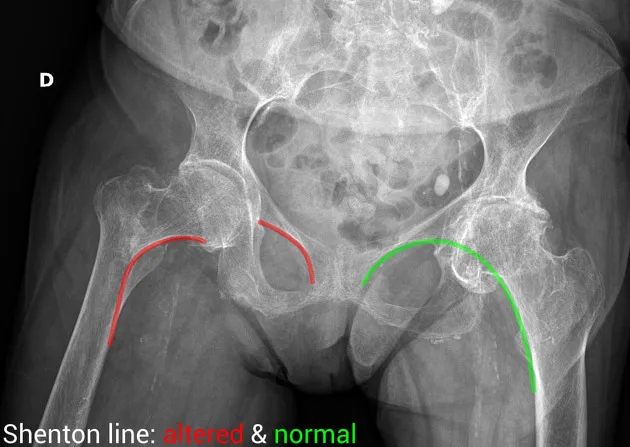

Shenton

What is seen in this image?

{{c1::Right neck of femur fracture}}

Case courtesy of Leonardo Lustosa, Radiopaedia.org. From the case rID: 98970

Normal Shenton line